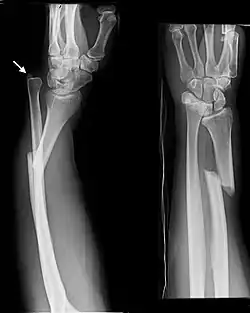

- Distal ulna fractures typically occur along with distal radius fractures.[3]

- Galeazzi fracture - not a fracture of the ulna but a displaced fracture of the radius accompanied by a dislocation of the ulna at the wrist, where the radius and ulna come together.[2]

Galeazzi facture (displaced fracture of the radius)